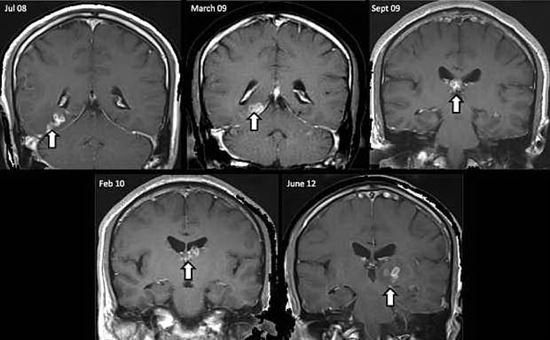

La storia di Luis Ortiz, studente californiano di 26 anni, poteva finire in tragedia. Il ragazzo, in preda ad una fortissima emicrania, si reca al pronto soccorso della città in cui vive. Qui la scoperta choc: nel suo cervello alberga una colonia di vermi. Da lì inizia la corsa contro il tempo dei sanitari che danno al giovane non più di mezz’ora di vita. Per Luis si aprono immediatamente le porte della sala operatoria. Le lastre effettuate prima dell’intervento evidenziano una situazione drammatica. Nel suo cervello vive un parassita che aveva prodotto una sacca di larve. Quest’ultima ha formato una cisti che blocca l’afflusso di acqua al cervello. “I medici – racconta Ortiz dopo l’operazione – lo hanno tirato fuori e hanno detto che si muoveva ancora. Ma come ha fatto un parassita a finirmi in testa?“. La risposta arriva dai saniatari che spiegano che questi parassiti possono introdursi nel corpo umano attraverso l’assunzione di cibi contaminati, come carne o pesce infetti.